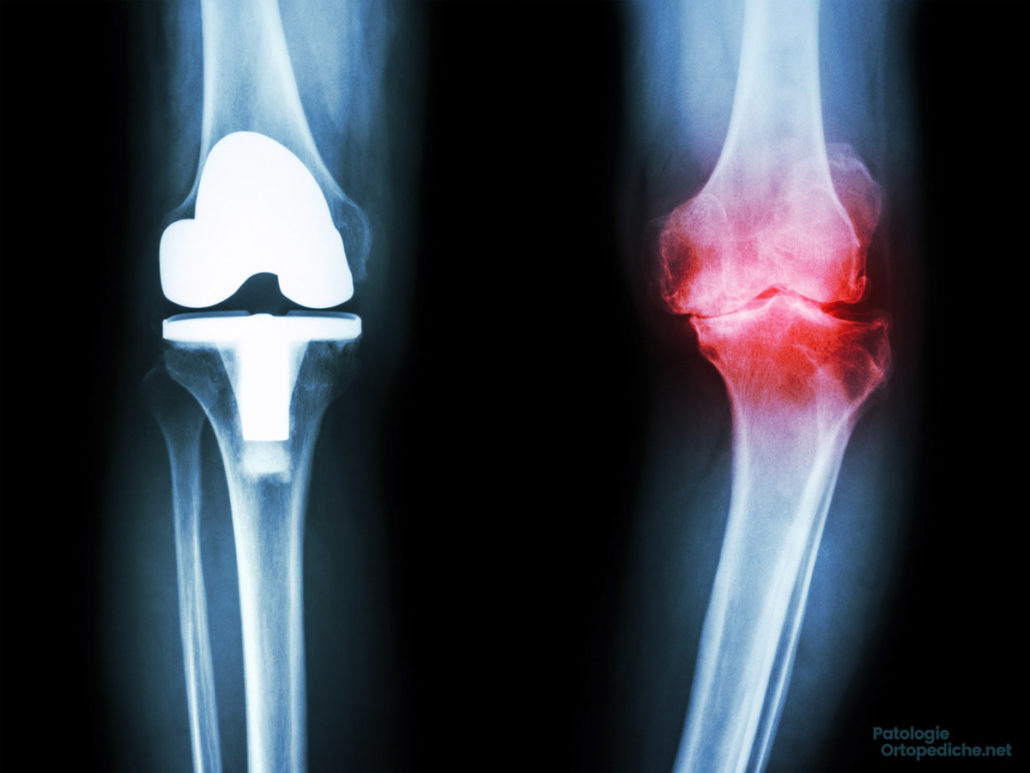

È la più comune malattia degenerativa da usura del ginocchio e consiste nella perdita della cartilagine di cui il ginocchio è rivestito al suo interno, fino ad esporre l’osso sottostante, provocando così dolore in particolar modo durante il cammino. L’osso può deformarsi ed il movimento si riduce notevolmente, la capsula articolare si ispessisce ed i muscoli si retraggono fino a determinare un ginocchio rigido, in genere semiflesso e curvo. Tipici della gonartrosi sono il gonfiore e la comparsa di cisti posteriori (cisti di Backer).

I sintomi di gonartrosi non vanno trascurati: il problema non è il dolore, bensì il dolore è la spia che deve farci allarmare ed intervenire precocemente. Una gonartrosi sottovalutata porterà nei casi più gravi a dover intervenire chirurgicamente con l’innesto della protesi